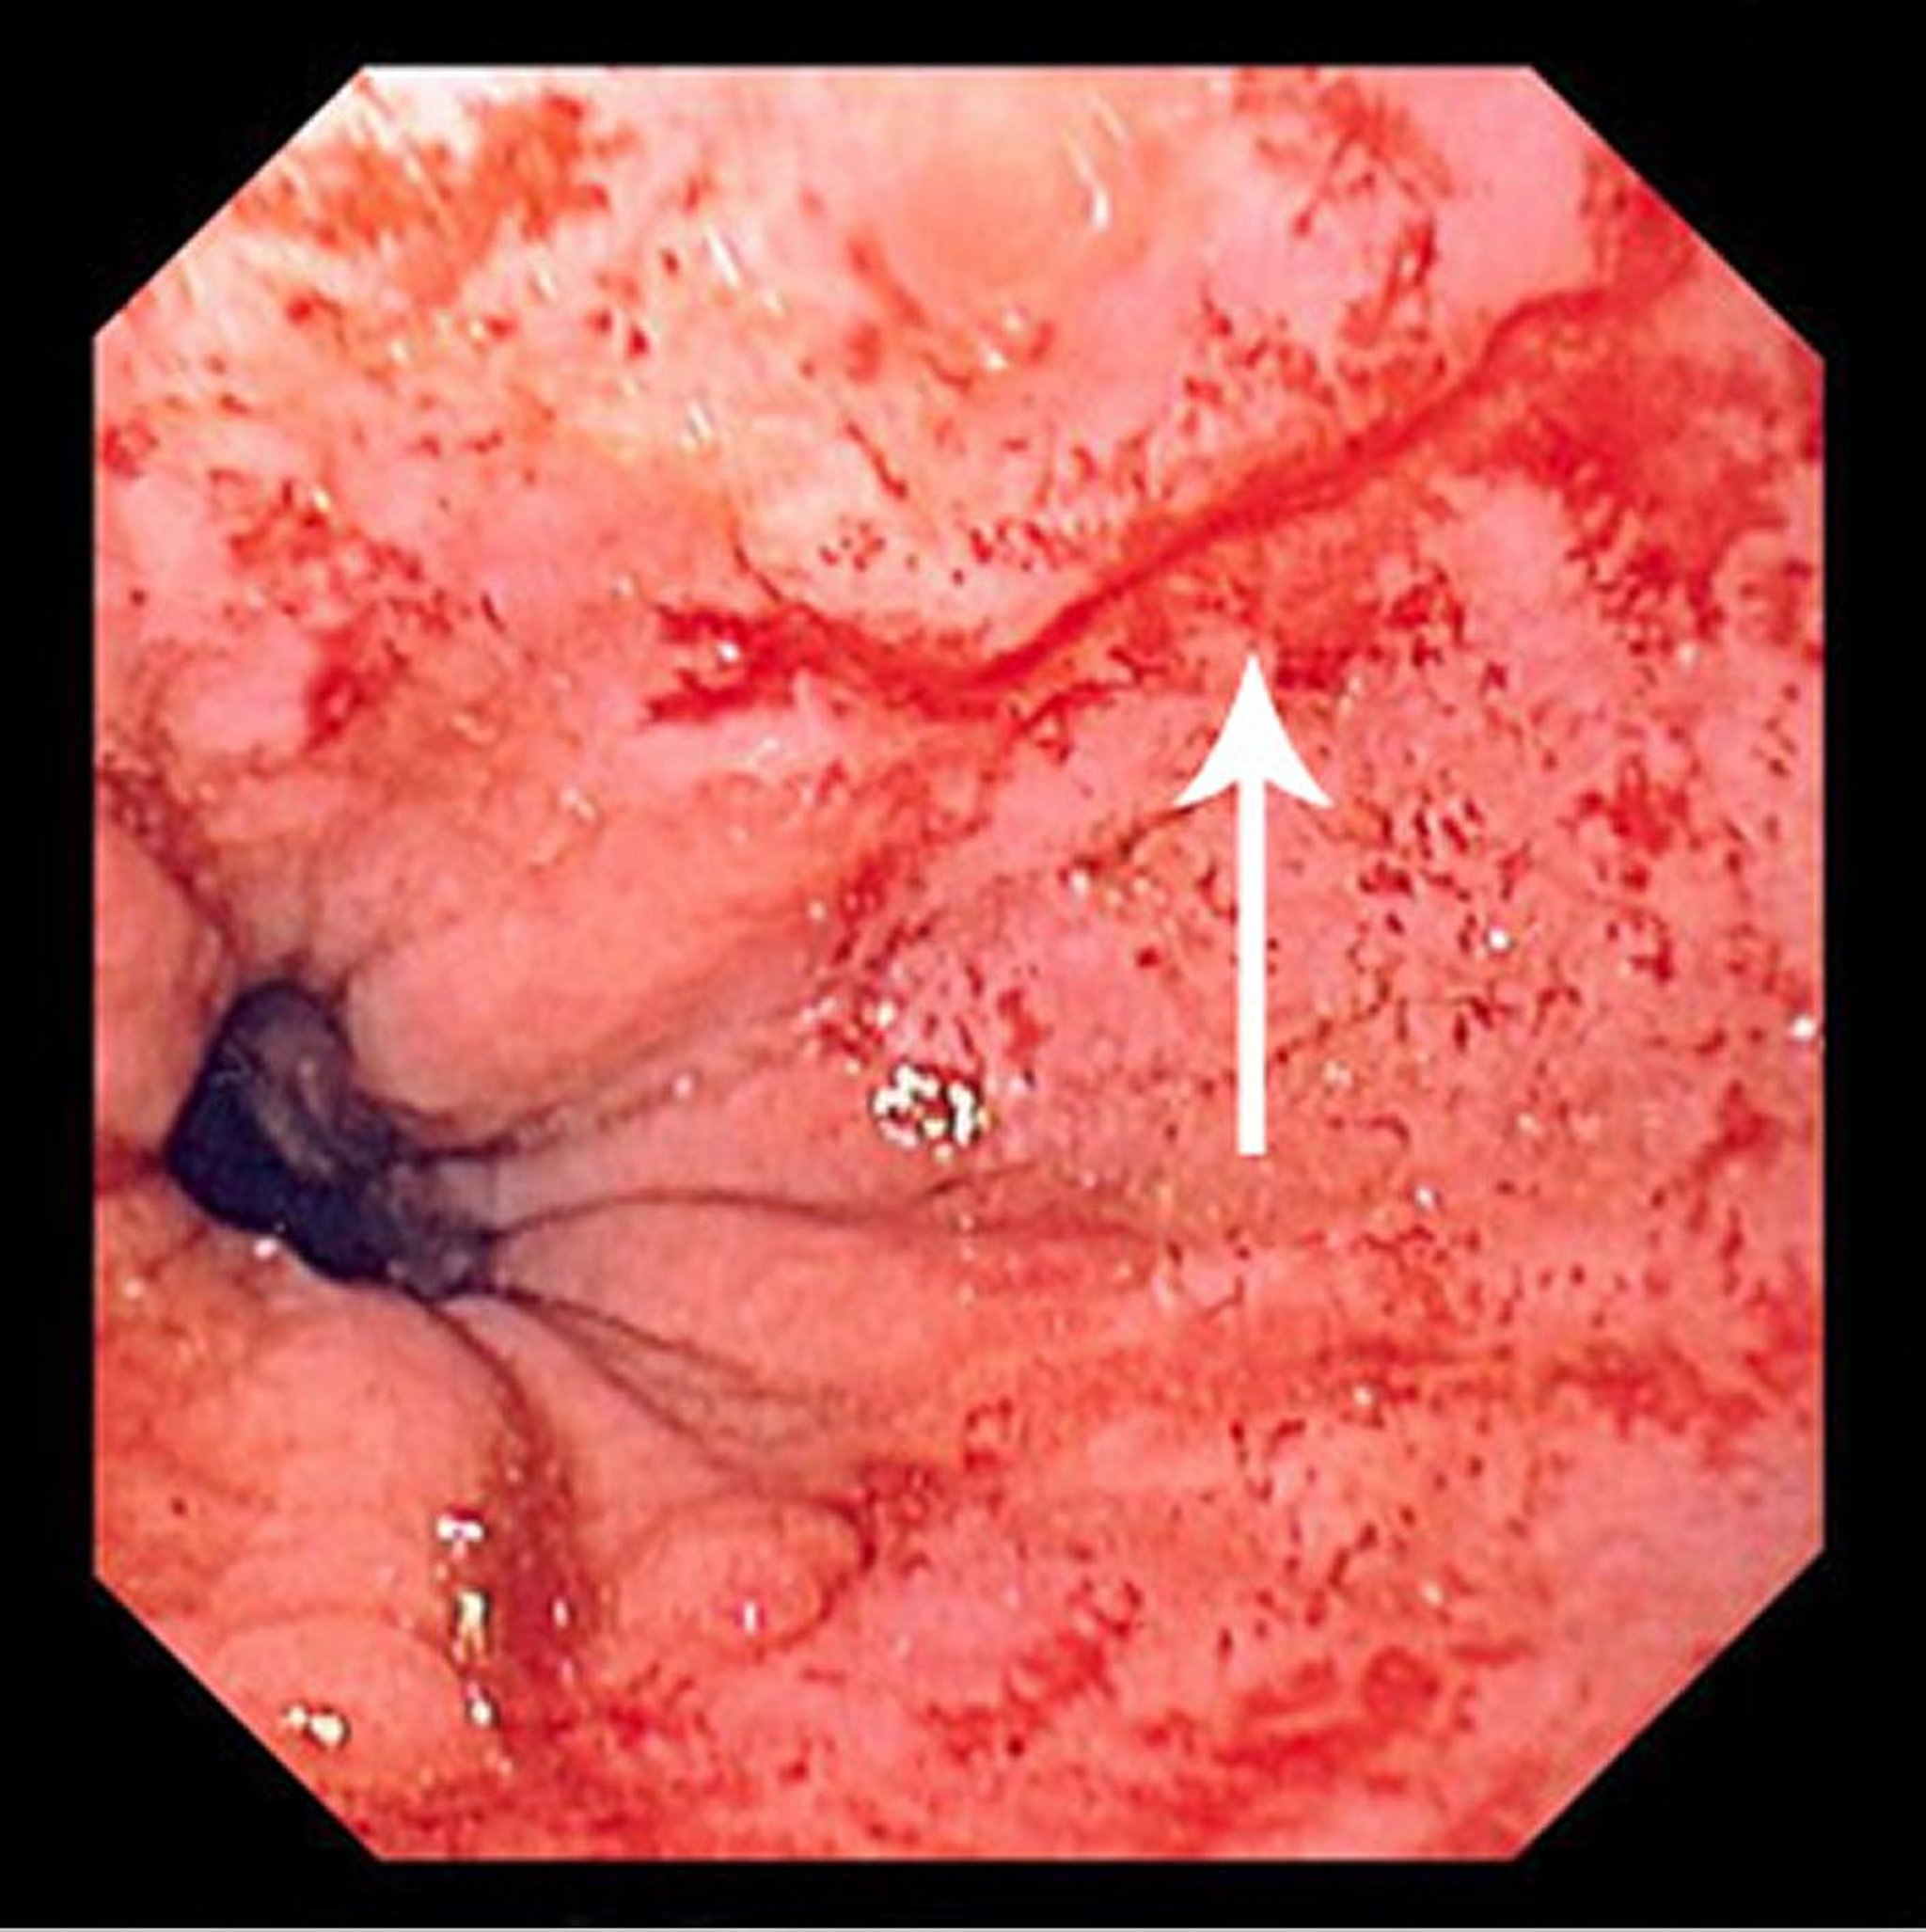

Синдром Маллори-Вейсса

На данной фотографии представлен небольшой разрыв (стрелка) Маллори-Вейсса.

Фотография предоставлена д-ром Дэвидом М. Мартином (David M. Martin, MD).